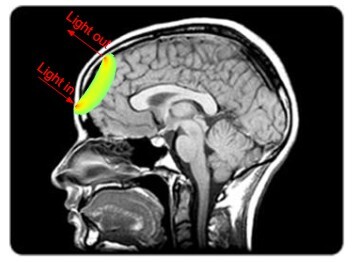

Open-MOTION uses a technique called pulsed speckle contrast optical spectroscopy, or PSCOS.3 When coherent laser light enters tissue, it scatters off moving red blood cells and other structures, producing a pattern of bright and dark spots – a speckle pattern. The contrast of that pattern is directly tied to how fast blood is flowing: faster flow means lower speckle contrast, slower flow means higher contrast. By firing short pulses of near-infrared laser light at the head and capturing the resulting speckle patterns, Open-MOTION measures changes in cerebral blood flow with high temporal resolution.

The device operates at 785 nanometers, a wavelength chosen because it sits near the isosbestic point for hemoglobin – the point where oxyhemoglobin and deoxyhemoglobin absorb light equally. That means the measurement reflects total blood flow rather than being confounded by oxygenation state. From the raw speckle data, the system derives two key metrics: relative blood flow from changes in speckle contrast, and relative blood volume from changes in average speckle intensity.

The headset is placed on the patient. The near-infrared laser fires short pulses of coherent light into the region of interest. The camera captures the resulting speckle patterns at high frame rates. The system generates cerebral blood flow waveforms – continuous traces of how blood moves through the vasculature, based on relative changes in speckle contrast over time.